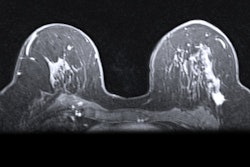

Researchers from Austria found that nonscanning parameters affect workflows on abbreviated breast MRIs. They compared exam ratios when nonscanning parameters are included and excluded in imaging protocols. Image courtesy of Dr. Philipp Stelzer.The group found that abbreviated examination protocols lead to a much smaller number of screenings than expected. Stelzer and colleagues calculated the number of exams possible if nonscanning parameters were included.